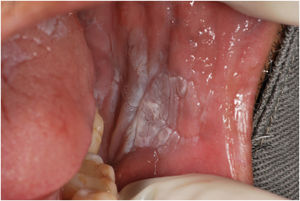

A 57-year-old male patient, a smoker (15 cigarettes a day for 43 years), showed, four years before, a painless white plaque with a slightly verrucous surface, approximately 3 cm in size, located on the left buccal mucosa (Fig. 1). Given the appearance of the lesion, the diagnostic hypothesis was leukoplakia. An incisional biopsy was performed, and smoking cessation instructions were given. Microscopic examination revealed high-grade epithelial dysplasia, corroborating the clinical diagnosis of leukoplakia (Fig. 2). Considering the lesion location and extent, the treatment of choice was complete excision using High-Power Diode Laser (TW Surgical Laser, MMOptics, São Carlos-SP, Brazil), delivering the beam with a 400 µm optical fiber, 808 nm wavelength (infrared) in continuous mode and 1.5 W power. The procedure was performed under local infiltrative anesthesia with 2% mepivacaine with vasoconstrictor (1.8 mL). For postoperative care, oral analgesics (1 g dipyrone every 12 hours in case of pain) and 0.12% chlorhexidine digluconate mouthwash, three times a day, for 14 days were prescribed. After seven days, the area appeared raw and painless (Fig. 3). After 30 days, no recurrence was observed, and complete healing of the area was noted. After 18 and 30 months (Fig. 4), clinical examination revealed no recurrence of the lesion. Despite instructions regarding smoking cessation, the patient still reports smoking, although less frequently. Therefore, continuous follow-up is essential.